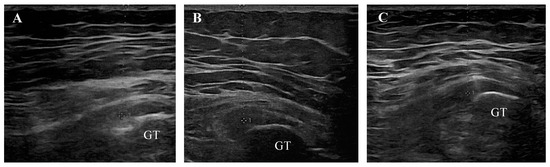

- Manske, R.C.; Wolfe, C.; Page, P.; Voight, M.L.; Bardowski, E. The Utilization of Diagnostic Musculoskeletal Ultrasound in the Evaluation of Gluteus Medius Tendon Pathology: A Perspective for Rehabilitation Providers. Int. J. Sports Phys. Ther. 2024, 19, 642–645. [Google Scholar] [CrossRef] [PubMed]